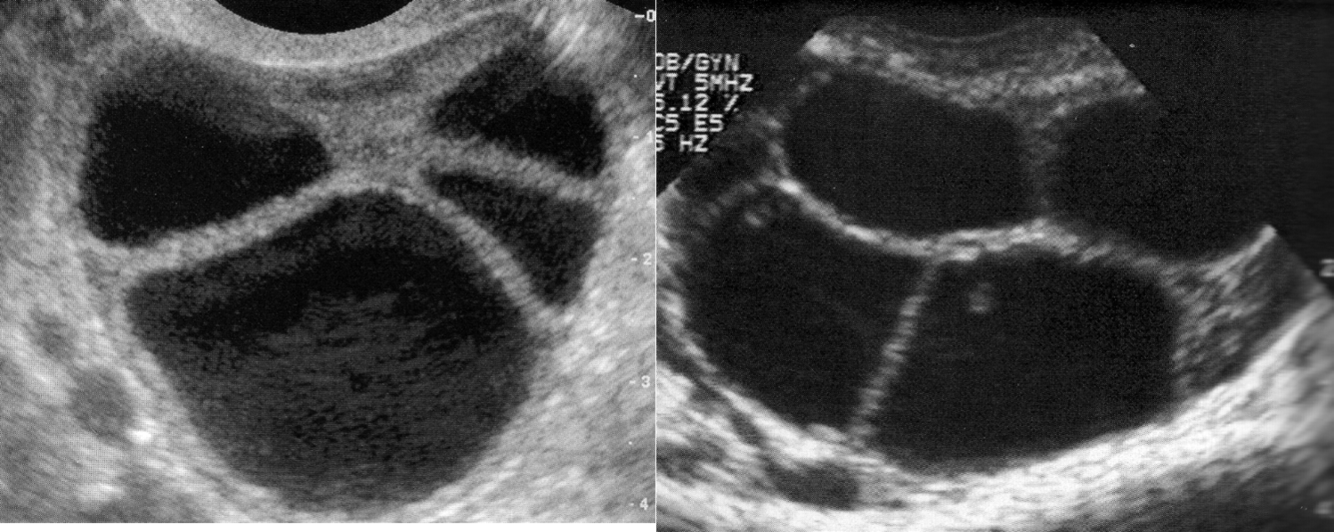

Ovarian Stimulation

Oocyte retrieval

US guided embryo transfer

Ovarian Hyperstimulation Syndrome